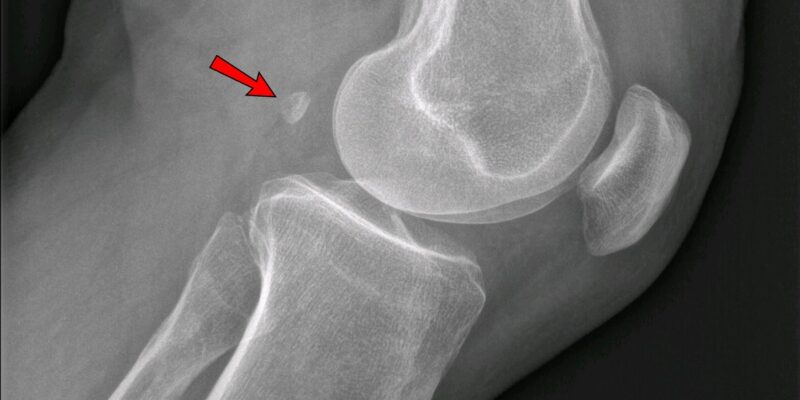

В теле взрослого человека 206 костей. Но иногда отдельные счастливчики могут отрастить ещё парочку — под коленными чашечками. Эти кости называются фабеллы. Они встраиваются в сухожилие икроножной мышцы.

Фабелла формируется не при рождении, а уже в довольно взрослом возрасте. Около 100 лет назад эти маленькие кости образовывались всего у 7,64% населения, но исследования 2019 года показали, что теперь фабеллы есть уже у половины людей.

Учёные не уверены, зачем фабеллы нужны. Может быть, они не делают ничего и даже приносят дополнительные боли людям с артритом. Но также есть вероятность, что фабеллы уменьшают трение в сухожилиях под коленной чашечкой, увеличивая механическую силу мышцы.

Возможно, это следствие того, что люди за последнее время начали лучше питаться и стали крупнее и тяжелее, а колени так к этому адаптируются.